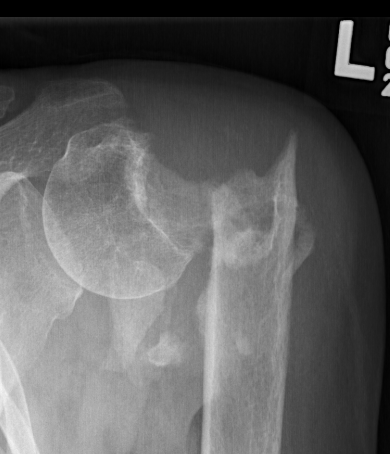

Severe comminuted proximal humerus fractures

100% displaced / off ended

Fracture - dislocations

Unreconstructable fracture - 4 part, comminuted, head spltting fracture

hemi failed

Loss of tuberosity fixation